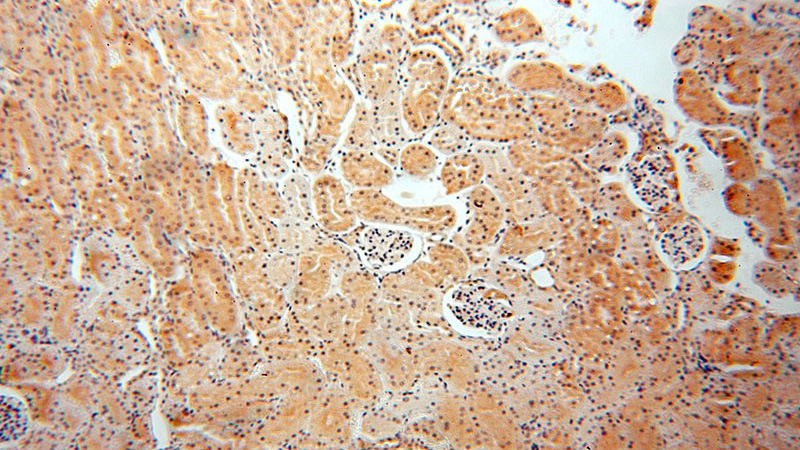

Immunohistochemical of paraffin-embedded human kidney using Catalog No:113518(OTUD7B antibody) at dilution of 1:50 (under 10x lens)

Immunohistochemical of paraffin-embedded human kidney using Catalog No:113518(OTUD7B antibody) at dilution of 1:50 (under 40x lens)